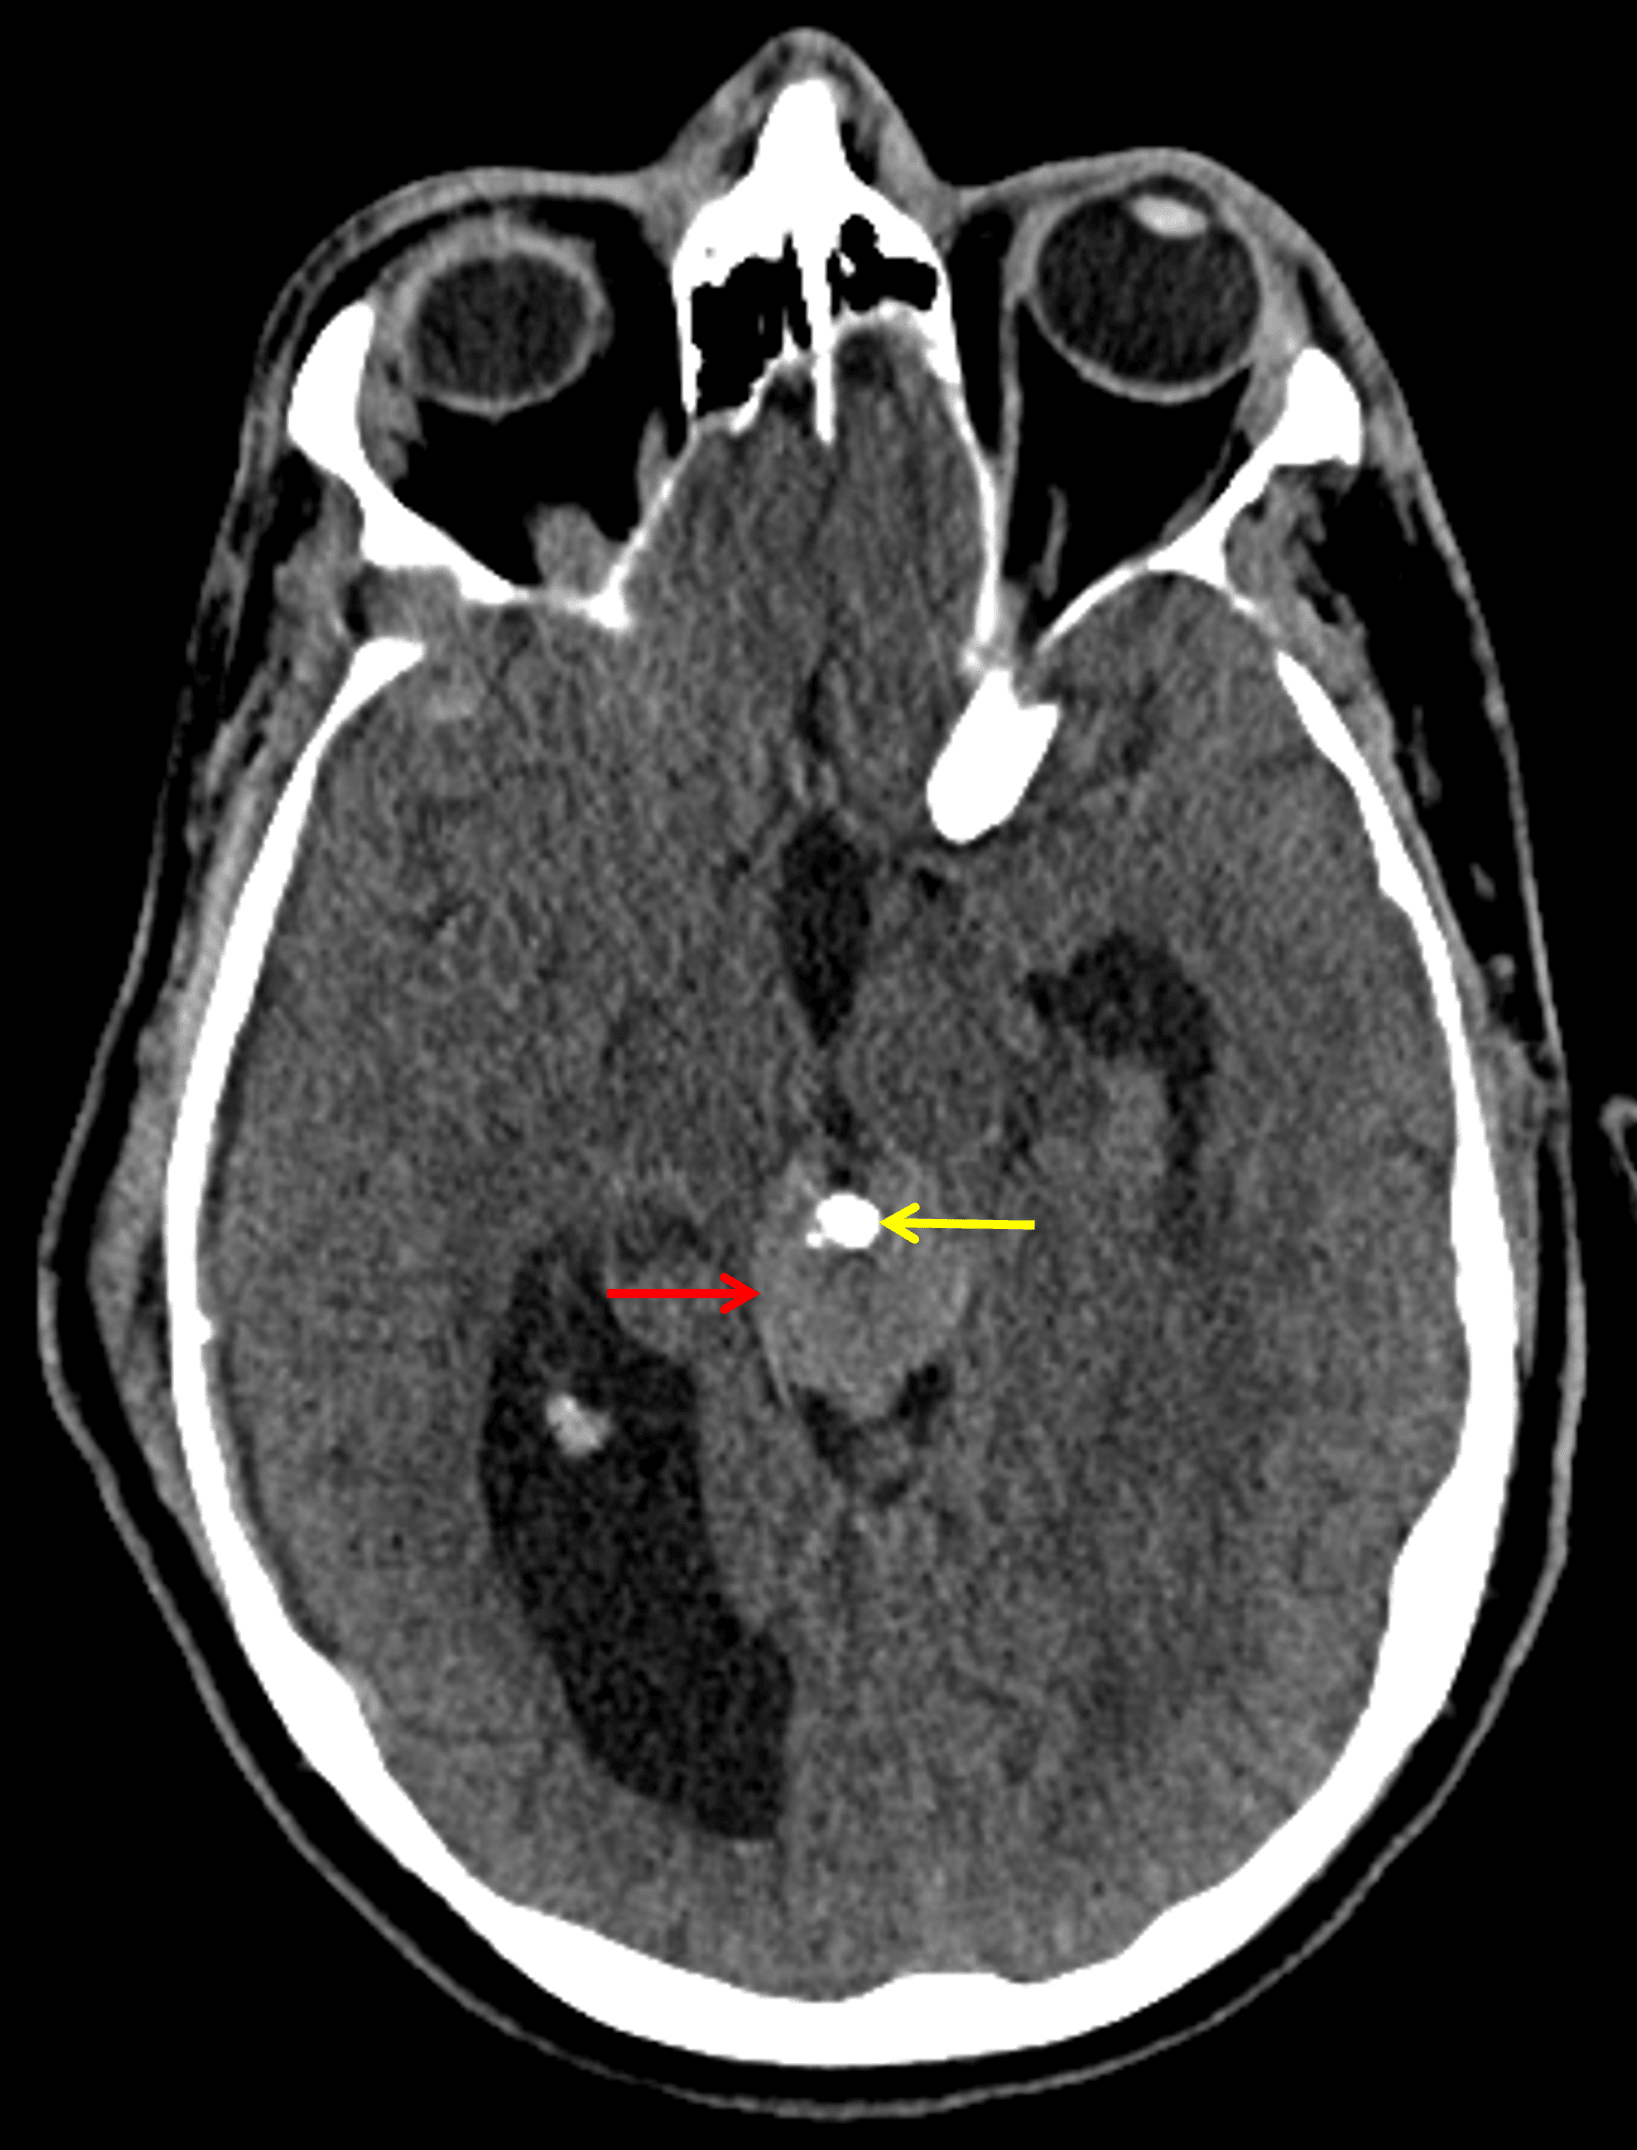

CT

- Mildly hyperattenuating pineal region mass with internal calcification

- Associated obstructive hydrocephalus at the level of the cerebral aqueduct

- Right frontal approach external ventricular drain terminating in the third ventricle

Mildly hyperattenuating pineal region mass (red arrow) which engulfs the pineal calcification (yellow arrow).